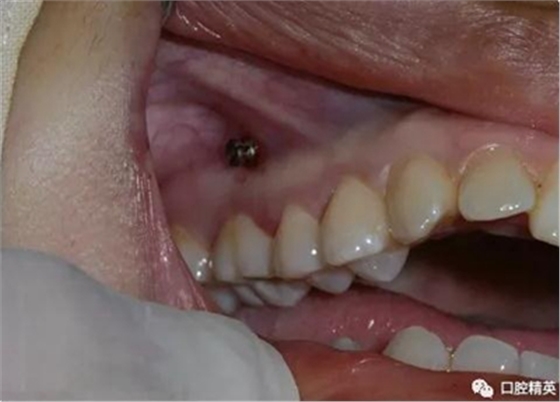

再次,植入微型種植體,在附著牙齦處不需要粘骨膜翻瓣,在牙槽黏膜處則需要切開黏膜以避免植入時(shí)軟組織被卷入,植入部位通常在膜齦結(jié)合部位或偏根方2~3mm,植入角度與骨面垂直并傾斜15~20度,即向根尖方向植入,術(shù)后拍根尖片以確認(rèn)與牙根的關(guān)系。術(shù)后口服抗生素預(yù)防感染并進(jìn)行口腔衛(wèi)生宣教。

上頜種植釘?shù)闹睆?.6,長度11mm;下頜直徑2.0,長度9mm

1、上頜種植釘常見位置在5,6之間;下頜種植釘常見位置在6,7之間。